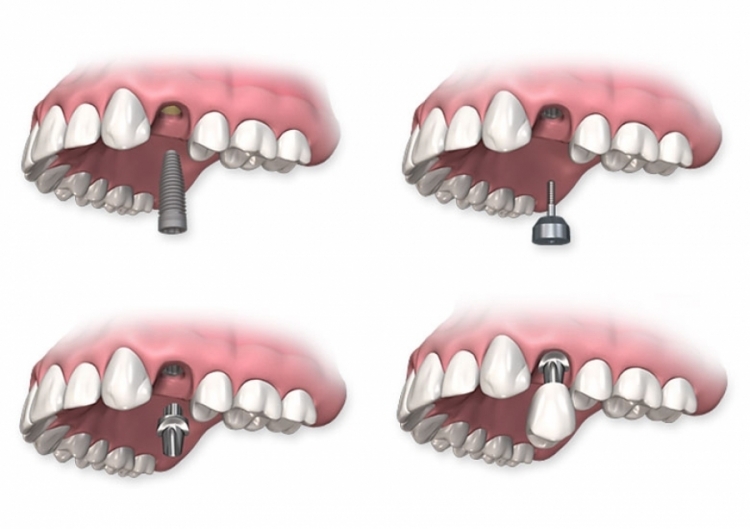

Sostituzione di un singolo dente

A differenza di altre soluzioni per la sostituzione di singoli denti, gli impianti non influenzano i denti adiacenti e ne rispettano l’integrità.

Questo è il motivo per cui gli impianti dentali rappresentano la scelta migliore.

Che cos’è un impianto dentale?

Un impianto dentale è una radice artificiale, realizzata in titanio o ceramica di zirconio, che funge da base per il nuovo dente artificiale.

Sopra questa radice artificiale (l’impianto) si monta la corona del dente artificiale. Il risultato finale è un dente completamente artificiale che comprende:

Impianto dentale

Perno o connettore

Perno o connettore, la parte che unisce l’impianto dentale alla corona

Corona dentale

Corona dentale, fatta di metallo-ceramica o ceramica pura senza metallo